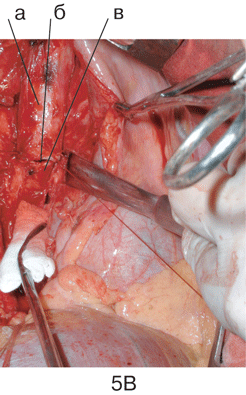

Рисунок 5. Этапы пневмонэктомии справа с циркулярной резекцией бифуркации трахеи

А. Мобилизация бифуркации трахеи: а — трахея; б — на держалке левый главный бронх, в — опухолевый конгломерат, в который замурован корень правого легкого.

Б. Вид операционной раны после удаления правого легкого и бифуркации трахеи, дыхание больного осуществляется через катетер высокочастотной вентиляции, проведенный в левый главный бронх: а ;– трахея; б — левый главный бронх.

В. Формирование анастомоза (б) между трахеей (а) и левым главным бронхом (в)